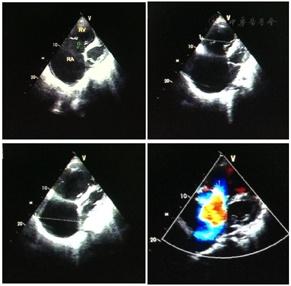

入院后完善检验提示三大常规、凝血六项、肾功能、血气分析、心肌损伤标志物及BNP正常。而肝功能检验提示:ALP、GGT、TBil等显著增高,提示肝功能异常。胸部X片提示:心界明显扩大,心胸比约为0.81(图1)。心电图提示:心房颤动;电轴右偏;完全性右束支阻滞;心脏顺钟向转位;T波改变窦性心律,T波低平(图2)。进一步完善心脏彩超:左心房32 mm、左心室40 mm;右心房横径100 mm、上下径106 mm;右心室前后径65 mm、横径81 mm、上下径62 mm;肺动脉主干24 mm,右室流出道60 mm;右心室EF 34%;左心室EF 66%,室壁未见节段性运动异常;三尖瓣:瓣环52 mm,关闭时瓣口对合差,反流面积37 cm2,流速190 cm/s,压差15 mmHg(图3)。腹部彩超:肝脏:右叶斜径16 mm,肝段面增大,肝静脉明显增宽(右支2.4 mm,中支2.2 mm,左支2.0 mm);下腔静脉内径4.0 mm;胆囊壁粗糙增厚;胰、脾及双肾未见异常。

手术前后彩超对比提示右心显著缩小,提示治疗后患者右心结构得到恢复。手术前后胸部X片对比提示心影缩小,心胸比从0.81下降到0.72。结合患者心功能、后期复查结果,提示冠脉重建后右心心肌血供恢复,心肌重塑,大小恢复。术后3个月复查心电图:阵发性房性心动过速(房室传导比例呈2:1传导);电轴右偏;完全性右束支传导阻滞;ST-T改变。通过治疗患者右心大小逐渐恢复正常,心功能恢复,日常生活无明显受限,规律服药、定期复查中,对治疗效果满意。